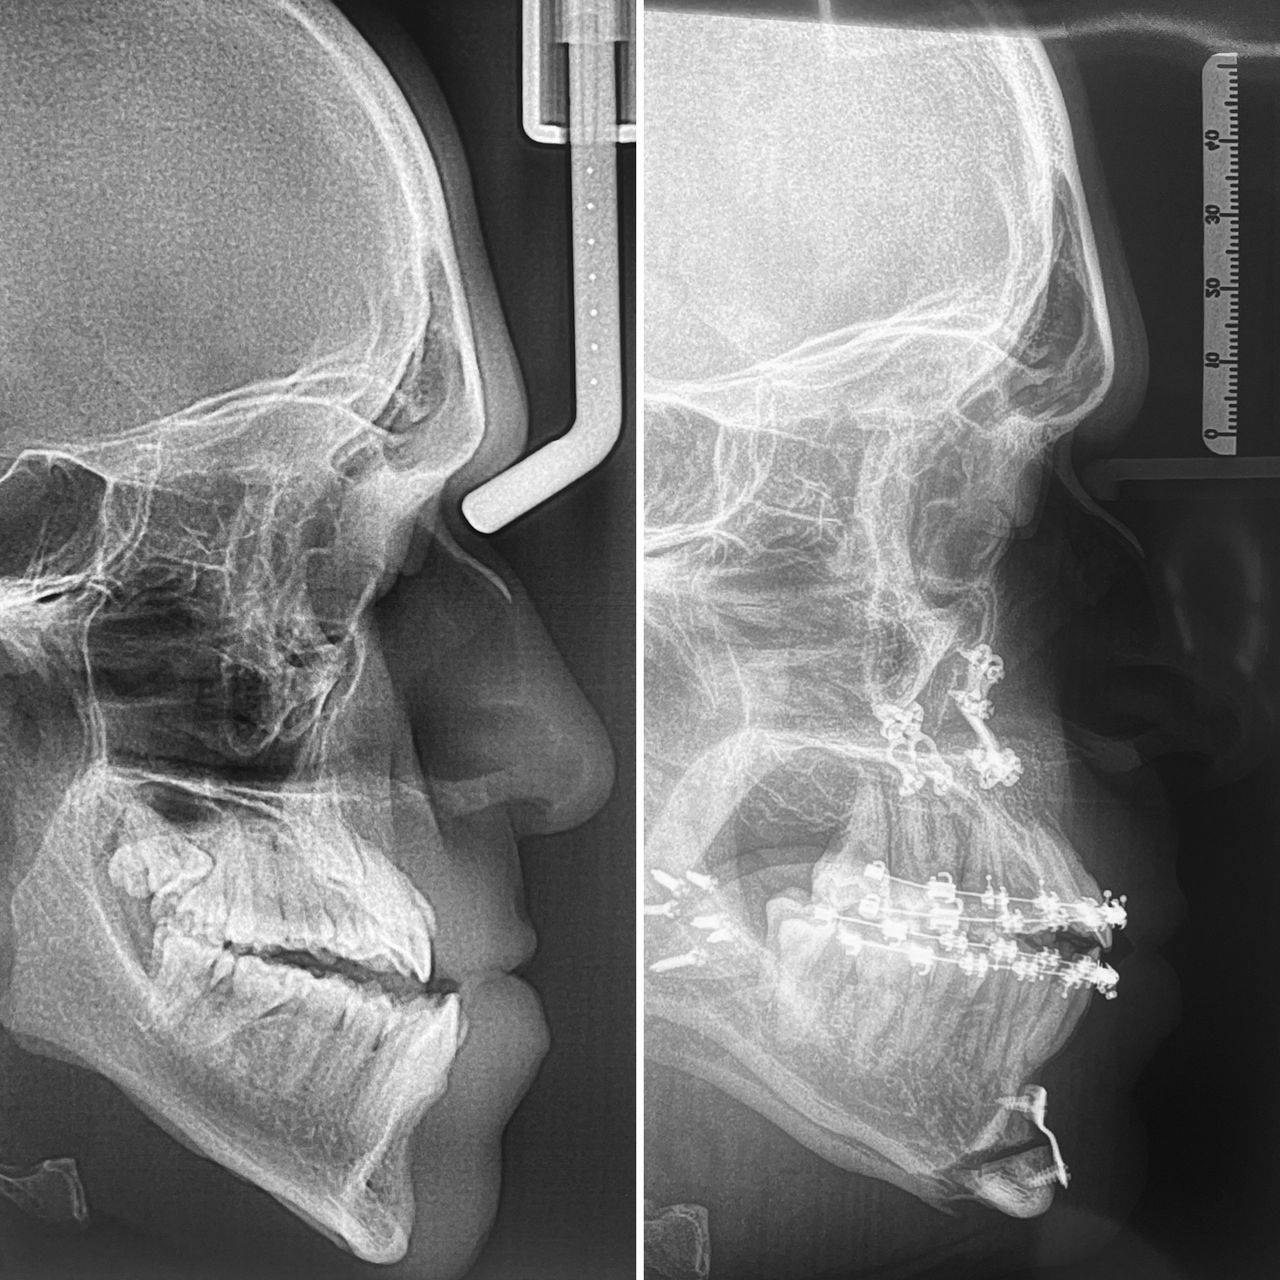

Cuento con experiencia en procedimientos de cirugía oral como: exodoncias simples, exodoncia de dientes incluidos y terceros molares, biopsias, frenillectomias, implantes dentales, implantes cigomáticos, implantes yuxtaoseos, regeneración ósea y tisular guiada.

En el área de cirugía maxilofacial tengo experiencia en el manejo quirúrgico de trauma facial, anomalías dento-faciales, disfunción de articulación temporomandibular, reconstrucción de maxilares, Cirugía estetica Facial, blefaroplastia, otoplastia, mentoplastia, Lifting facial, Lip Lift y reposicionamiento labial, retiro de biopolimeros en cara y Armonización Oro-Facial.

I have experience in oral surgery procedures such as: simple extractions, extraction of impacted teeth and third molars, biopsies, frenectomies, dental implants, zygomatic implants, juxta-osseous implants, and guided bone and tissue regeneration.

In the field of maxillofacial surgery, I have experience in the surgical management of facial trauma, dentofacial anomalies, temporomandibular joint dysfunction, mandibular reconstruction, facial cosmetic surgery, blepharoplasty, otoplasty, mentoplasty, facelifts, lip lifts and lip repositioning, removal of facial biopolymers, and orofacial harmonization.

- Cirugía ortognática